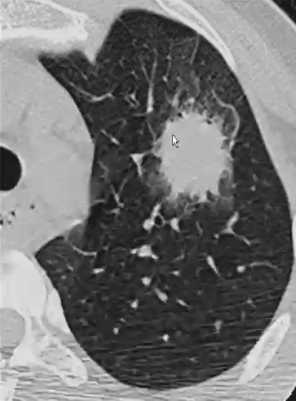

晕征(halo sign,HS)

❖ 定义:实性结节(梗死)周围可见磨玻璃影(出血)环绕